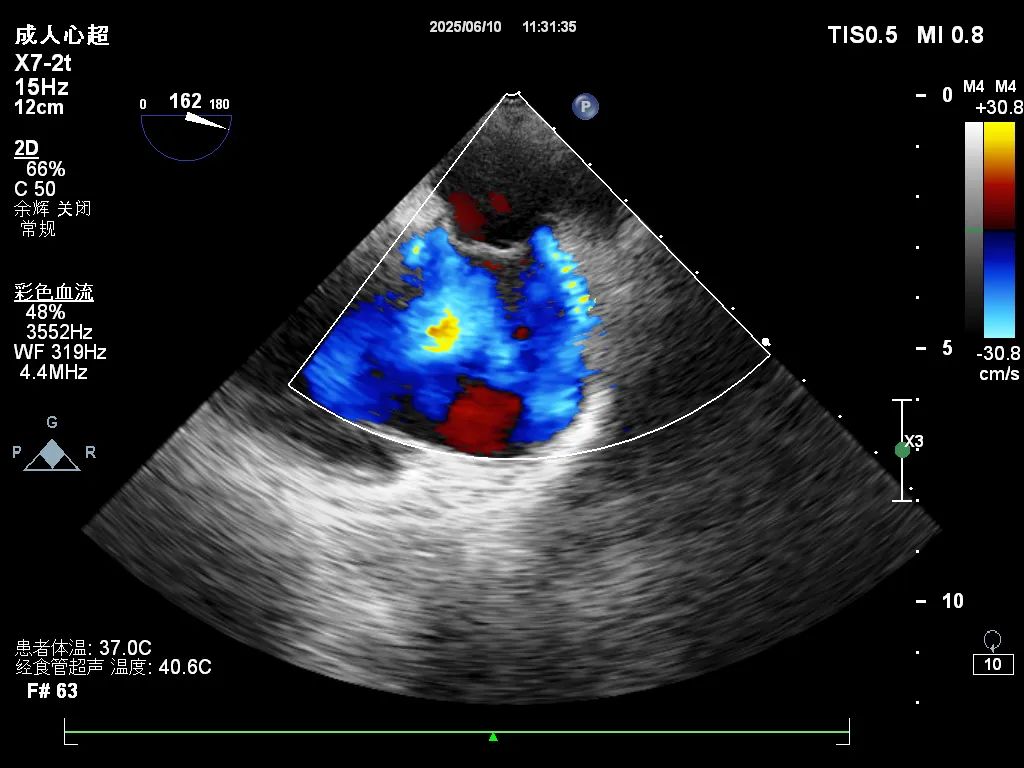

近日,我院功能检查科成功开展经食道超声心动图(TEE)检查新技术,进一步提升了我院心血管疾病的诊断水平。

经食道超声克服了传统经胸超声的局限性,通过食道从后方近距离探查心脏,显著提高了心房、房间隔及心脏瓣膜的图像分辨率,尤其适用于各类心脏瓣膜病、先天性心脏病、心耳内血栓及感染性心内膜炎等疾病的精细诊断,为手术方案的制定和术后评估提供了重要依据。

此项技术由王鹏医生率先开展,他曾赴北京安贞医院专项进修经食道心血管超声技术,积累了丰富的操作与诊断经验。目前,该技术已顺利应用于多名房颤及可疑卵圆孔未闭患者,检查过程安全、结果精准,受到临床医生和患者的一致好评。